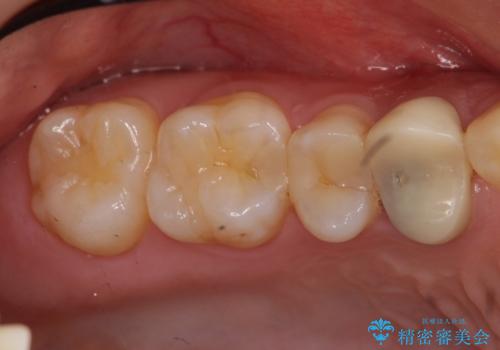

他院の根の治療で一向に治らない、さらに歯根を切ってもらったが良くならない

- 他院で保険治療で根の治療に1年以上通っているが一向によくならないとのことでした。

根の詰め物をした後も歯ぐきからウミが出てくる上に、咬むと痛いとのことでした。

さらに、同じ病院で根の先を切る手術も行なったが症状が改善しなかったそうです。

前回の治療がうまくいかなかった原因として、根の中がまだ汚い状態で、根の先だけを切ってもうまくいかない可能性があったことを説明し、根管治療をやり直すことになりました。